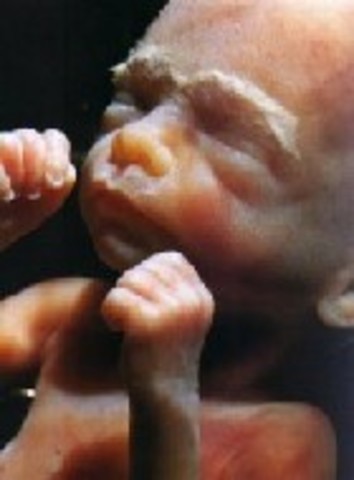

Embryo is now called a Fetus. Muscles are almost finished developing and fingerprints on skin are begining to form.

• Week 11

Week 11

Fingers and toes are seperate. Fetus can awallow and stick out tongue. Gender is begining to be defined.